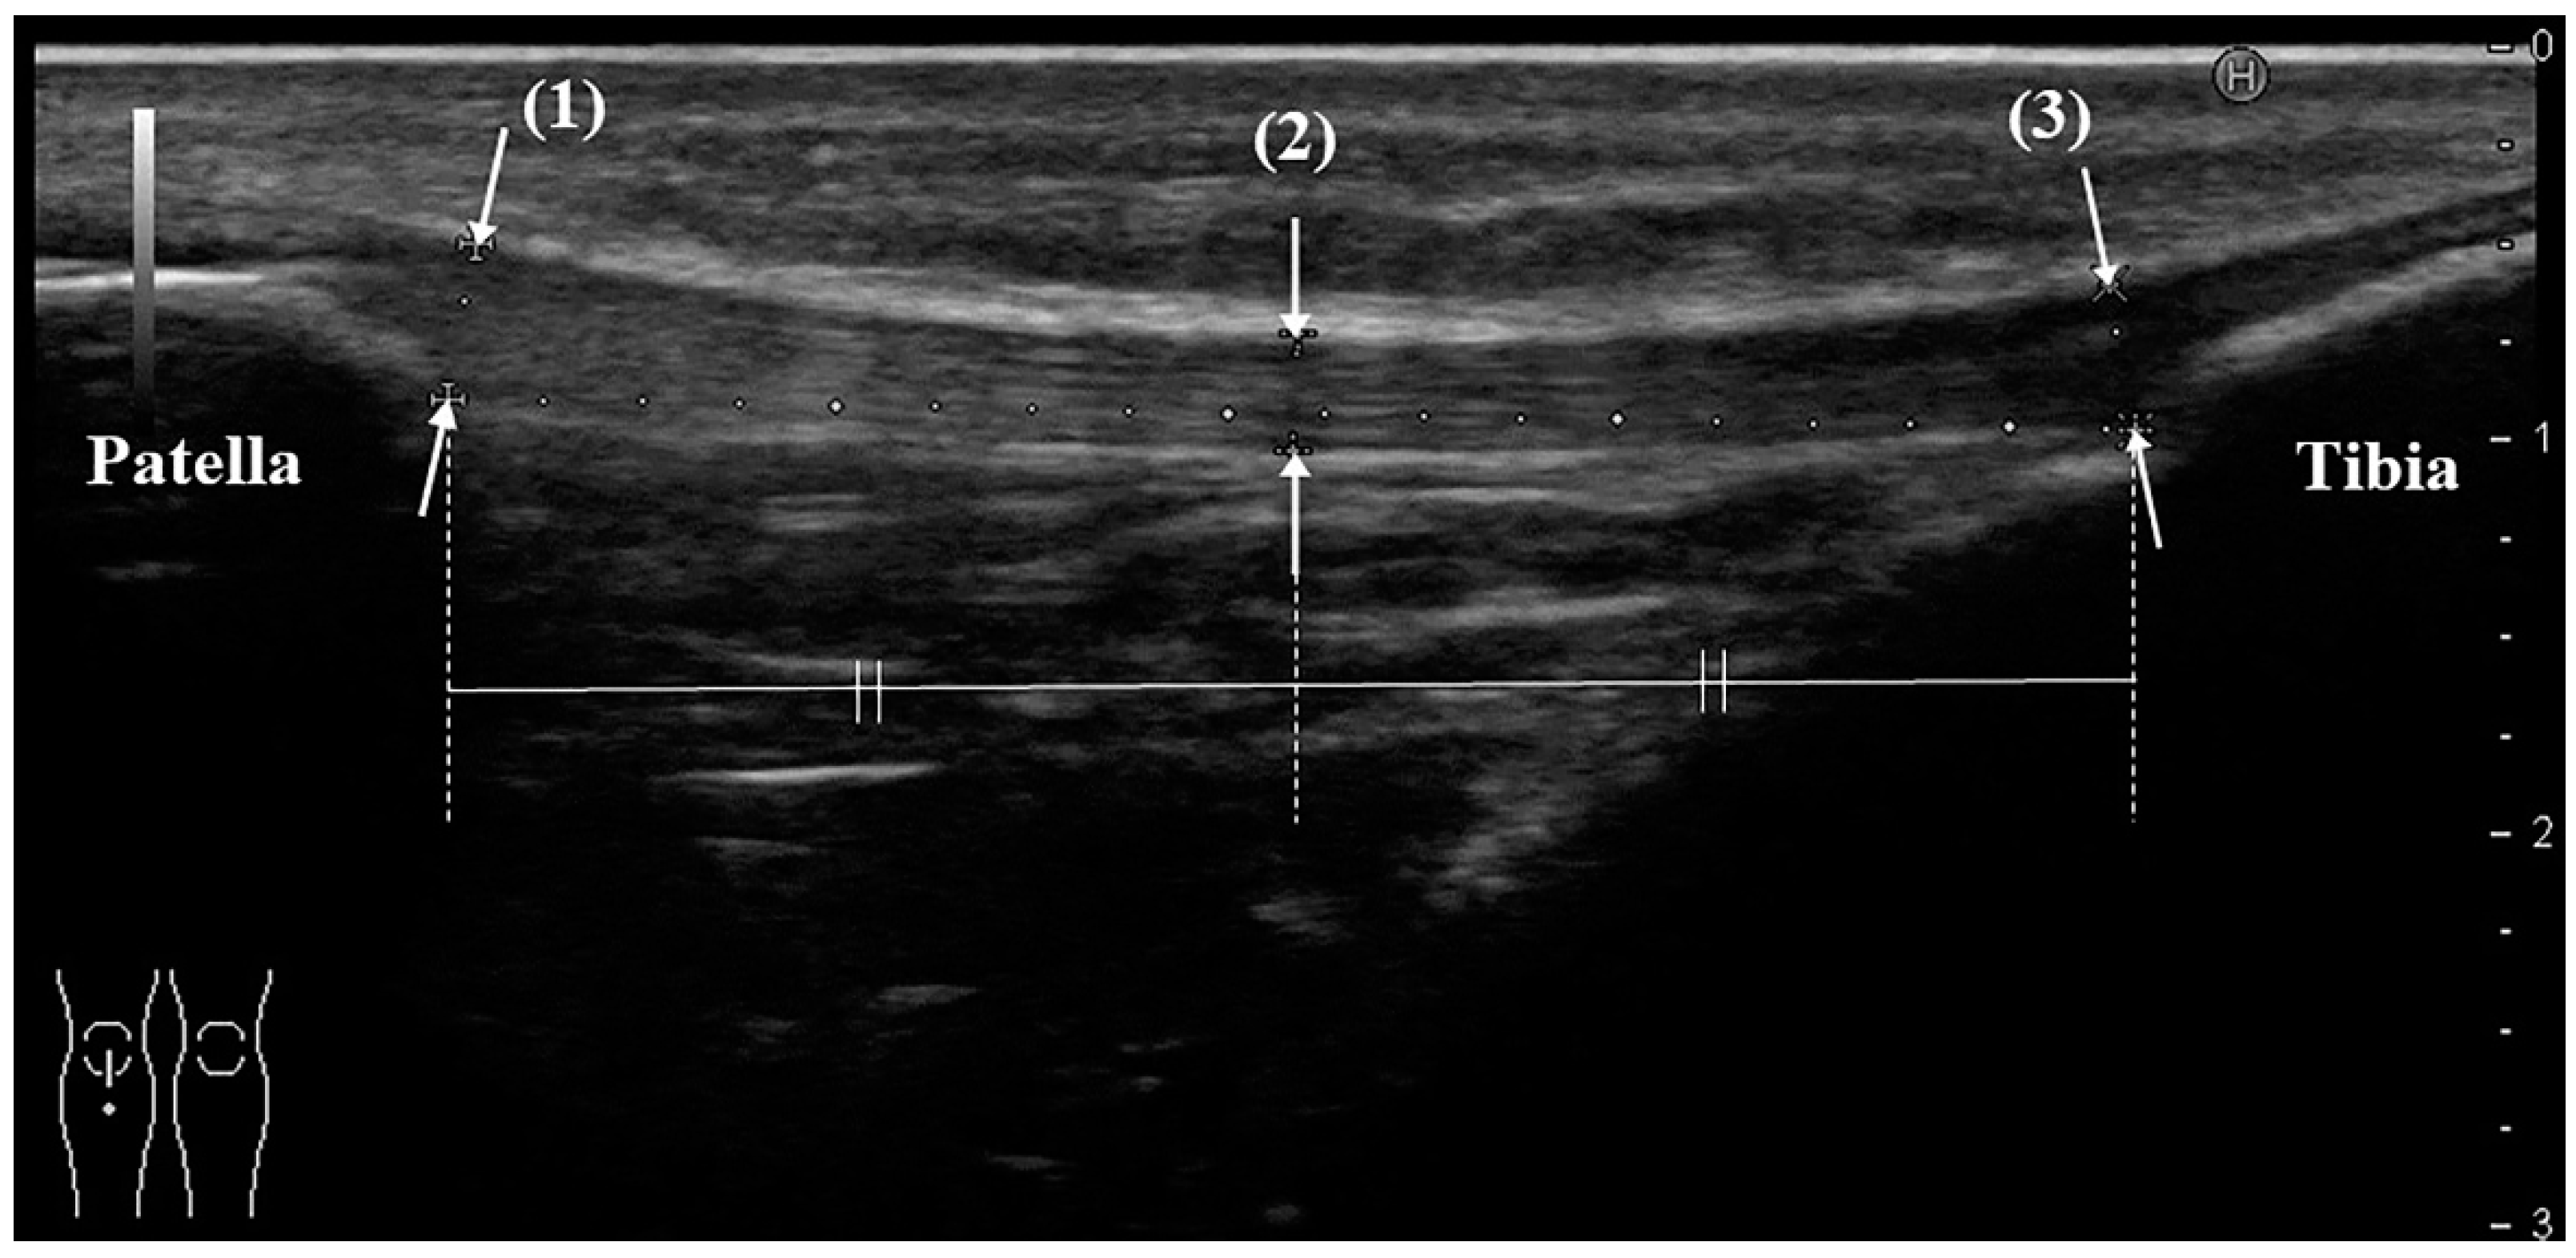

US was performed by the same orthopedic surgeon, who has more than 8 years of clinical experience and who routinely uses ultrasound equipment. The instrument was a HI VISION Preirus (Hitachi Medical Corporation, Kashiwa, Chiba, Japan) and an EUP-L53 linear probe (frequency 7.5 MHz, visual field width 64 mm; the total length of the patellar tendon can be evaluated in 1 slice). The participant was placed in the supine position, and a knee flexion of 30 degrees was achieved by using a knee pillow. Evaluation of the patellar tendon began with the probe being placed at the point where the tendon meets the body surface, and a long-axis image following the entire length of the tendon was drawn. On ultrasound, the tendon should show the typical echogenic, fibrillar pattern and extend from the inferior patella to the tibial tuberosity. The tendon thicknesses at the proximal end, midpoint, and distal end were measured (Figure 1). The measurement was performed 3 times per knee, and the average value was used.

Figure 1. Measurement method of patellar tendon thickness with ultrasonography (long-axis image). Thickness is defined as the distance from the superficial to the deep layers of the tendon, measure at: (1) the proximal part: the point where the deep layer of the tendon is attached to the lower end of the patella; (2) the midpoint between the proximal and distal parts; and (3) the distal part: the point where the deep layer of the tendon is attached to the tibial tubercle. All schemes followed the same formatting.